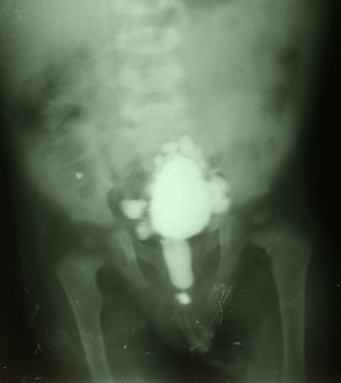

A preterm male infant was delivered by lower uterine cesarean section, with a history of polyhydramnios in the mother. The newborn infant developed repeated episodes of vomiting with regurgitation of feeds since birth. A diagnosis of congenital pyloric atresia was made for which he underwent gastroduodenostomy (Figure 1) on the fifth day of life. He also developed bullous lesions over the trunk and extremities, with new lesions developing with trivial trauma (Figure 2) (Figure 3). At six months of age, the child developed poor stream of urine with discharge of whitish flecks with fever. Urine culture was positive for Pseudomonas aeruginosa, sensitive to gentamicin. Ultrasound showed hydronephrotic changes in both kidneys with dilatation of bilateral ureters. He was diagnosed to have posterior urethral valve (Figure 4) for which vesicostomy (Figure 5) had to be done after attempts of cystoscopy guided valve fulguration were deemed ineffective in a setting of recurrent urinary tract infection and hydronephrosis. The child presented with respiratory distress and hoarseness at four and a half years of age. Thereafter, direct laryngoscopy was done which revealed multiple masses occupying bilateral false cords, left aryepiglottic fold and anterior commissure (Figure 6). The masses were firm, fleshy, pedunculated and did not bleed on touch. Biopsy was taken and surgical excision of the masses was done. The histopathology examination revealed squamous papilloma (Figure 7). The child again presented with acute severe respiratory distress with cyanosis two months following discharge, for which emergency tracheostomy had to be done. Attempts of weaning were tried but the child was unable to tolerate it. At present, the child is 9.5-year-old, tracheostomized, school-going with age-appropriate neurodevelopment. His 6.5-year-old sister underwent gastroduodenostomy for congenital pyloric atresia on 21st day of life and vesicostomy for posterior urethral valve at two years of age. She was also diagnosed with junctional epidermolysis bullosa at four years of age. The mother of the patient also suffered from polyhydramnios during the birth of her second child. There is a history of sibling death within first week of life in his father’s generation following a blistering disorder.

Figure 4: Voiding cystourethrogram showing dilatation and elongation of posterior urethra and bladder trabeculation.